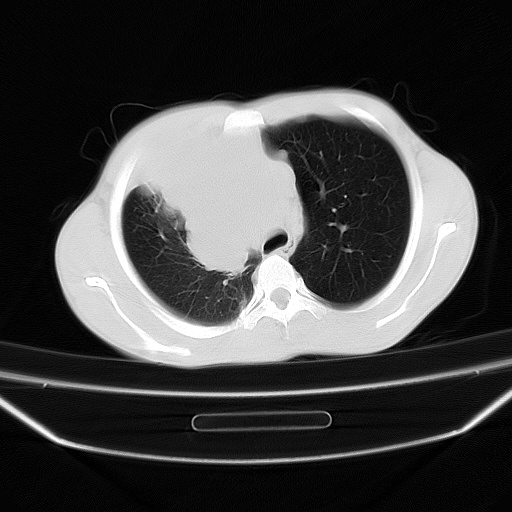

以下是引用zjzjr在2008-7-20 12:57:00的发言:[br]考虑为生殖源性肿瘤(内胚窦瘤),侵袭性胸腺瘤可能性大;右侧少量胸腔积液。

以下是引用xinliheng001在2008-7-20 21:17:00的发言:[br]右纵隔巨大分叶状软组织均质密度肿块,右上肺叶受压明显,纵隔右移、胸膜受累有少量积液和结节样增厚。应增强扫描一定会有更具诊断价值的信息。

以下是引用xinliheng001在2008-7-20 21:17:00的发言:[br]右纵隔巨大分叶状软组织均质密度肿块,右上肺叶受压明显,纵隔右移、胸膜受累有少量积液和结节样增厚。应增强扫描一定会有更具诊断价值的信息。